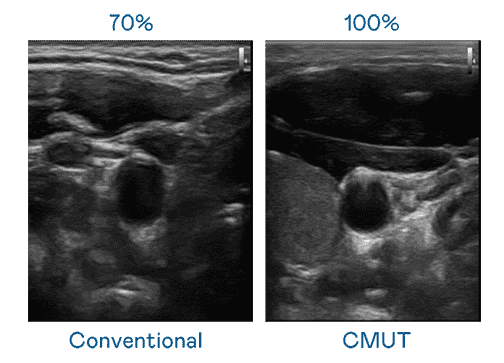

CMUT 技术是一种用电容式微机电元件来产生超音波讯号的技术。。。。与传统 PZT 压电式技术相比,,CMUT 频宽增加 30%,,,,更宽频的超音波讯号让影像解析度大幅提升,,,是实现高影像品质医疗超音波扫描、、、促进精准医疗发展的关键技术。。。

大频宽带来超清晰影像

超音波影像的解析度高低,,,首先取决于探头能发出的讯号频宽。。888.BY集团电子游戏 CMUT 可提供高清晰的超音波讯号,,,提供高频宽、、、、高灵敏度、、影像纹理细节更高的超音波影像,,,协助医护人员缩短影像判读时间及利用精准的医疗影像进行诊断。。。。